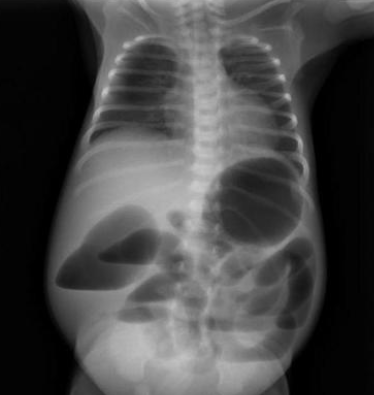

Q

Air-fluid levels on abdominal x-ray, heel prick/ sweat test to confirm cystic fibrosis